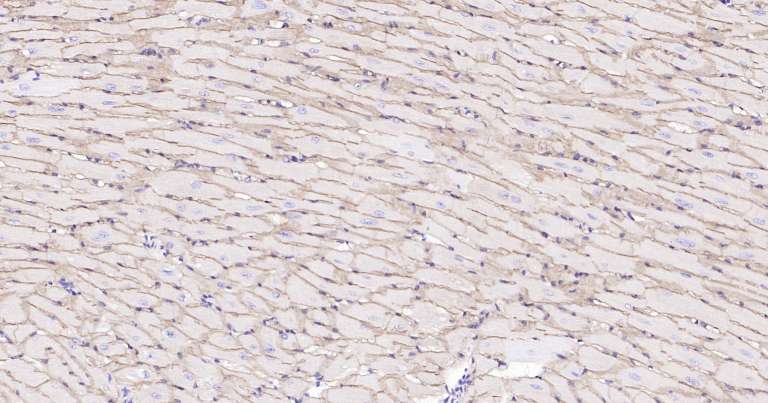

Immunohistochemical analysis of paraffin embedded mouse heart tissue slide using IHC0260 (Dystrophin IHC Kit).

Immunohistochemical analysis of paraffin embedded human heart tissue slide using IHC0260 (Dystrophin IHC Kit).

Immunohistochemical analysis of paraffin embedded rat heart tissue slide using IHC0260 (Dystrophin IHC Kit).